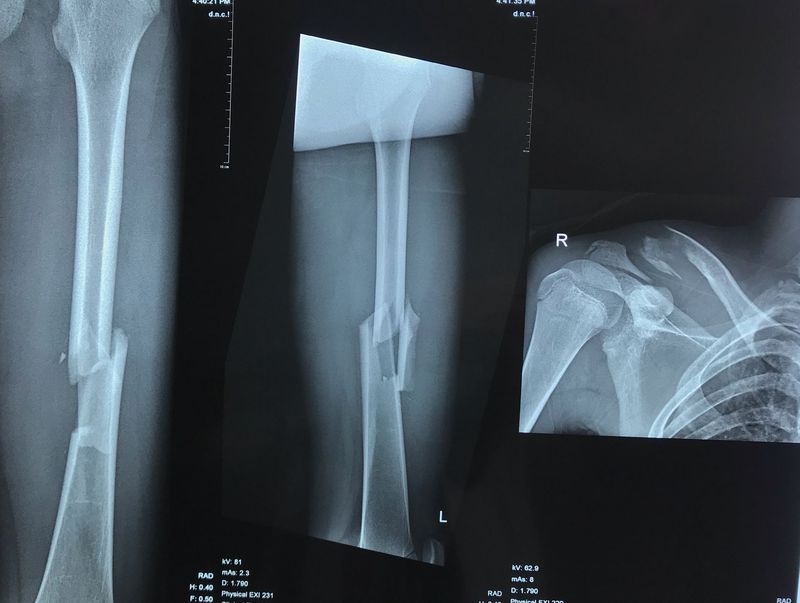

a man had a motorcycle accident, motorcycle collided with a truck. At the time of admission, the patient was compos mentis, gcs 15. However, he experienced limited movement in both hands. Crepitation (+) on the left arm. Open wound (-). Then take a photo of humerus and clavicle. What is the interpretation of the xray or what is the diagnosis?